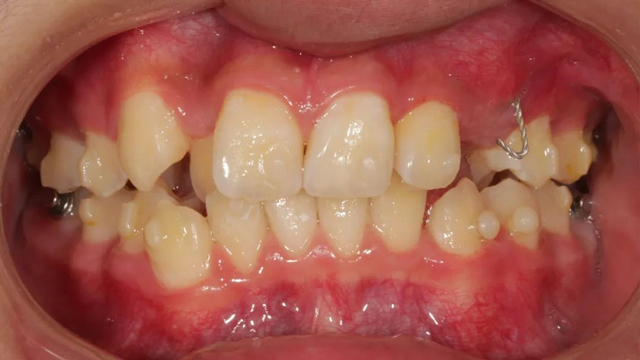

2021年8月(矯正前口內(nèi)照)

這位小患者的口腔問(wèn)題包括:牙列不齊,個(gè)別門牙反頜,左上尖牙完全埋伏阻生,另外,CBCT顯示右上門牙牙根腭側(cè)內(nèi)還有一顆多生牙。

簡(jiǎn)單地說(shuō),牙齒不整齊只是小問(wèn)題,他更大的問(wèn)題是:在不該長(zhǎng)牙的地方多長(zhǎng)了一顆牙,而乳尖牙滯留,早該替換出來(lái)的尖牙長(zhǎng)不出來(lái),這兩顆牙的問(wèn)題如果不及時(shí)干預(yù)治療,會(huì)帶來(lái)很多長(zhǎng)期的口腔問(wèn)題。

據(jù)了解,位于腭側(cè)的多生牙緊挨著已經(jīng)替換完的1號(hào)恒牙(門牙),如不拔除會(huì)影響整個(gè)牙列的整齊度,后期也可能損傷1號(hào)牙的牙根,導(dǎo)致這顆牙齒松動(dòng)甚至脫落。